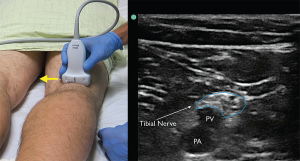

Figure 4. The tibial nerve sits just above the popliteal artery (PA) and popliteal vein (PV). Identification of this nerve is the first step in identifying the larger and more proximal distal sciatic nerve. Yellow arrow indicates direction of probe marker.